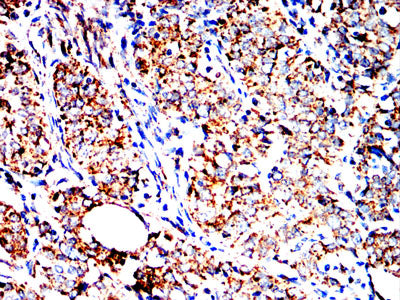

Immunohistochemical analysis of paraffin-embedded human cervical carcinoma tissues using HSPA9 mouse mAb with DAB staining.

Immunohistochemical analysis of paraffin-embedded human rectal cancer tissues using HSPA9 mouse mAb with DAB staining.